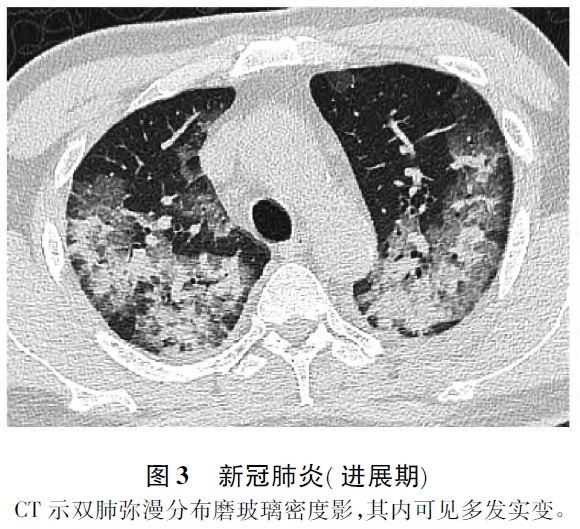

1. 2 进展期 随着病变进展,磨玻璃密度影范围逐渐扩大,密度逐渐增高。或融合成小叶性,或广泛融合呈带状或大片状密度增高影,其内支气管壁增厚,支气管血管束增粗,可见局部树芽征,亦可见网格状影。病变分布以双侧非对称性胸膜下楔形或扇形分布,肺底及背侧胸膜下区多见,部分沿支气管血管束分布。因肺泡内渗出液增多时磨玻璃密度影增高,实变时可呈软组织密度影或致密条索影(图3) ,呈节段性或小叶性分布[1-5]。一般无基础性疾病的患者多无胸腔积液、纵隔及肺门淋巴结增大。